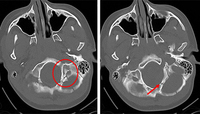

Fratura do osso temporal.

Do acervo de aulas de Demetrios Demetriades, Division of Trauma and Surgical Intensive Care, LAC/USC Trauma Center, Keck School of Medicine da USC; usada com permissão